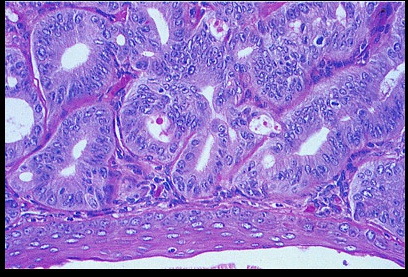

Endometrial hyperplasia pathway (75% of cases): patient with unopposed estrogen develops endometrial hyperplasia, which eventually advances to carcinoma. Average age is 60 years. Histology is endometrioid (normal endometrium-like). It is commonly driven by a PTEN mutation.

Sporadic pathway (25% of cases): carcinoma arises in an atrophic endometrium. There is no evident precursor lesion. Average age is 70 years. Histology is usually serous and is characterized by papillary structures with psammoma body formation. It is commonly driven by a p53 mutation, and the tumor exhibits aggressive behavior. (Necrosis > calcification > psamomma body)

Endometrioid. Looks like endometrium but disorganized with minimum stroma

Sporadic pathway. Serous.